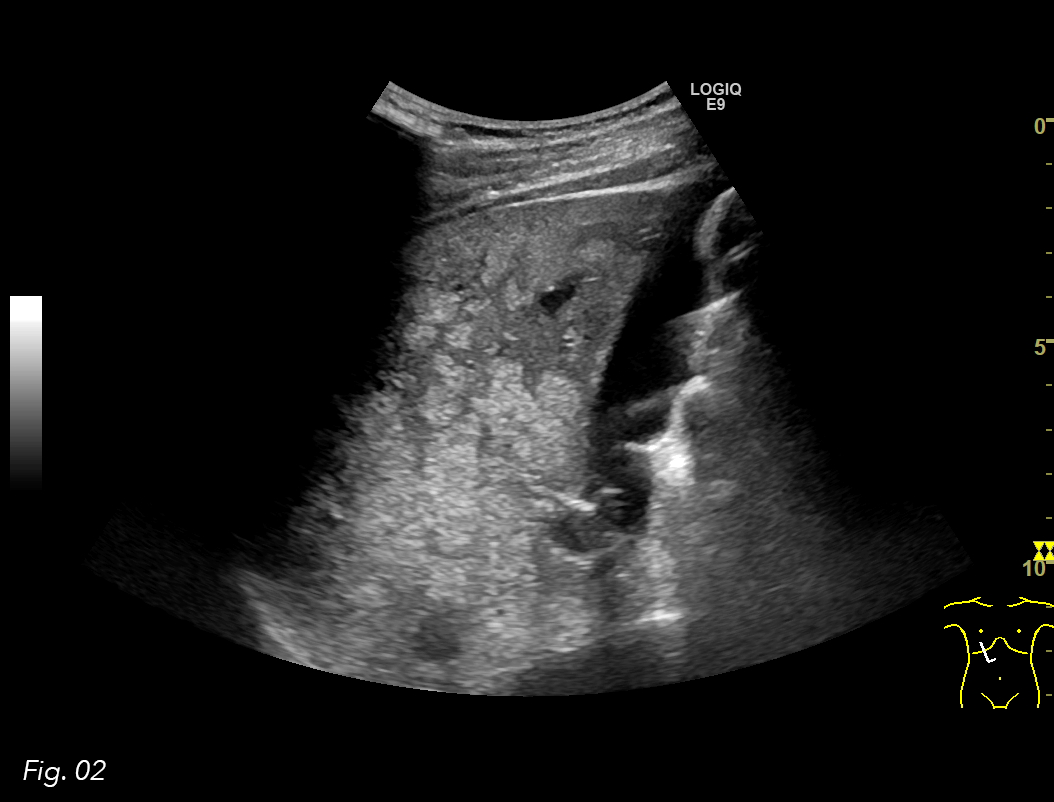

An ultrasound examination of the abdomen was performed using a GE Logiq E9 system with a curved array transducer and a frequency of 1-6 MHz. The patient was examined in the supine position. The examination revealed a large hyperechoic area in the liver hilum surrounding the portal vessels, involving segments IV, V and VIII. The lesion had an irregular borders, but the remaining liver parenchyma appeared normal (Fig. 1, 2).

Fig. 2: US image of the liver. Focal fatty infiltration in segment V next to the gallbladder.